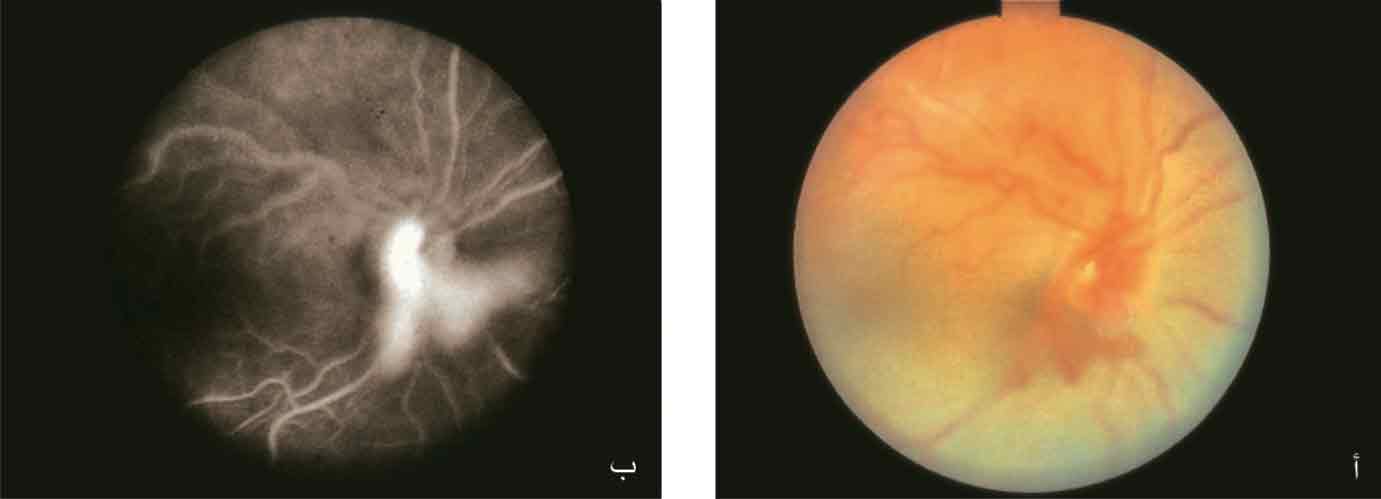

يتظاهر اعتلال العصب البصري بفرط الضغط الشرياني بصور مختلفة، ويرتبط ظهوره بإزمان فرط الضغط الشرياني أكثر من شدته. وقد يلاحظ لدى المرضى المصابين بارتفاع شديد في الضغط الشرياني نزوف خطية لهبية الشكل في المنطقة حول القرص البصري، وتغيم حواف القرص البصري، ووذمة واحتقان فيه مع ركودة شبكية وريدية ثانوية ونضحات ضمن اللطخة الصفراء (الشكل 4). ويتضمن التشخيص التفريقي للمرضى المصادف لديهم الصورة السريرية السابقة ما يلي: اعتلال القرص البصري سكري المنشأ، واعتلال الشبكية شعاعي المنشأ، وانسداد الوريد الشبكي المركزي، واعتلال العصب البصري الأمامي بنقص التروية، والتهاب العصب البصري والشبكية neuroretinitis.

(الشكل 4): تظهر الصورة (أ) قعر عين مريض مصاب بارتفاع ضغط شرياني شديد مع تدنٍ شديد في القدرة البصرية. يلاحظ وذمة القرص البصري والنتحات القاسية في اللطخة والنزوف الشبكية وبقع الصوف والقطن والاحتقان الوريدي. وتظهر الصورة (ب) قعر عين المريض نفسه بعد 10 أسابيع من ضبط الضغط الشرياني لديه مع تحسن القدرة البصرية وزوال وذمة القرص البصري ووجود بقايا خفيفة للنتحات القاسية في اللطخة.